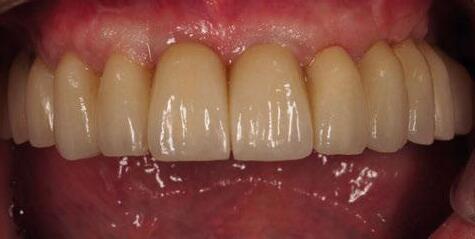

A los 4 meses, se retiró la prótesis provisional, verificando la

estabilidad de todos los implantes y procediendo a la toma de impresión definitiva, enviando toda la información necesaria, tanto de la posición de los implantes, de los perfiles de emergencia y pónticos y de la forma del provisional (Figuras 28 y 29).

Para ello, se procedió al escaneado mediante el escáner intraoral iTero Element™2 de los siguientes elementos: